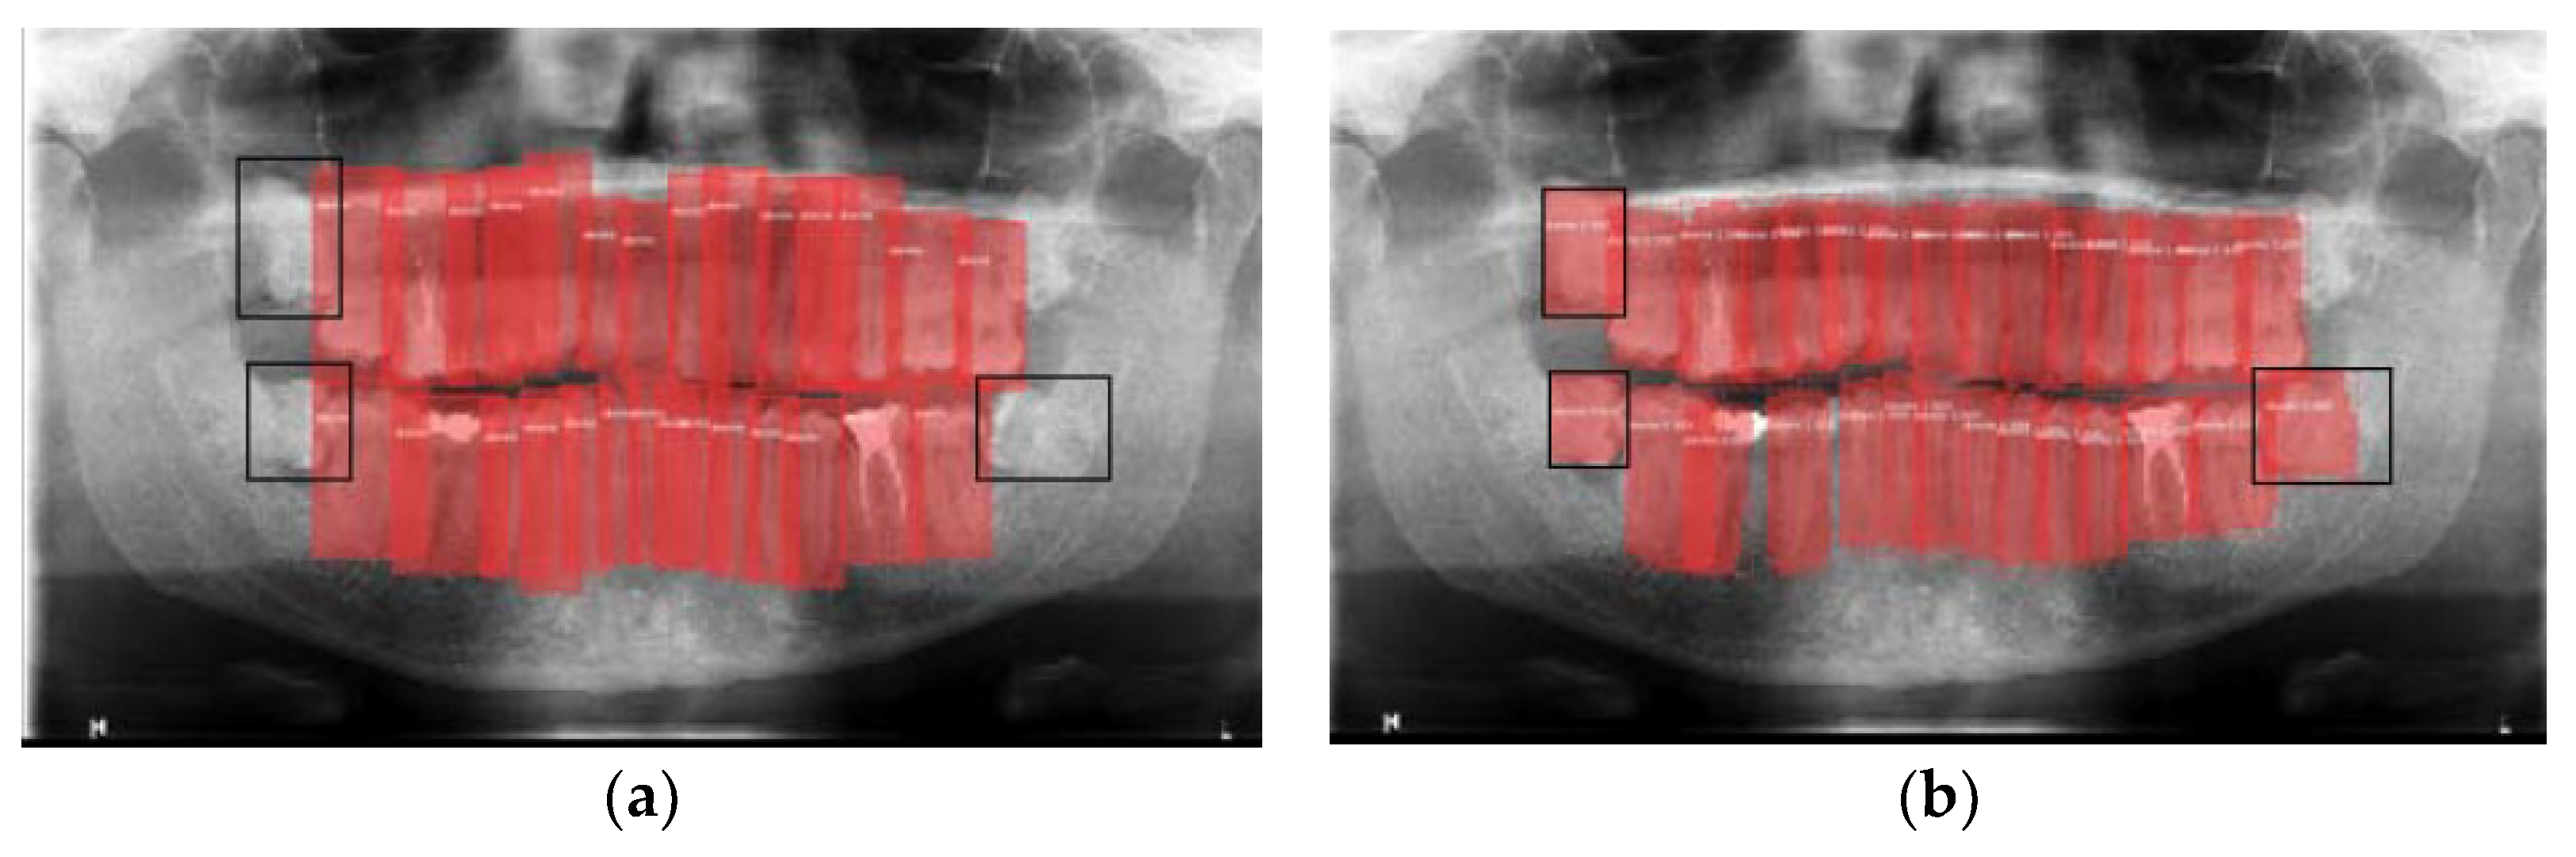

3.2. Teeth Detection Results

3.3. Some Interesting Examples

3.4. Model Execution Examples